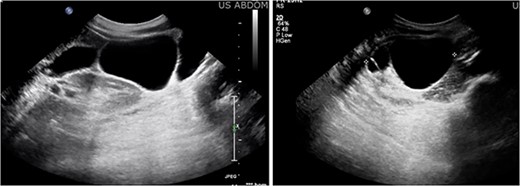

A 47-year-old female with no significant past medical history presented with right lower quadrant pain radiating to the back, which had persisted for 3 days. Additionally, she reported a 6 pound weight loss over the course of one year. She had no personal or family history of malignancy. Her labs were within normal limits and her CEA, CA 19–9, CA 125, and CA 27.29 were not elevated. A CT scan of the abdomen and pelvis (Fig. 1) revealed a multilobulated, multiseptated, well circumscribed cystic mass measuring 8.0 × 4.7 × 7.9 cm in size abutting the inferior aspect of the gallbladder extending anteriorly to the right kidney into the paracolic gutter. Ultrasound imaging (Fig. 2) revealed as multiseptated cystic mass measuring 4.4 × 7.7 × 9.3 cm, suspicious for exophytic complex hepatic cyst. No mural nodularity or abnormal mural hypervascularity was seen. Tumor markers LDH, CA 125, and CEA were within normal limits. The decision was made to perform a diagnostic laparoscopy with potential resection.

Ultrasound imaging revealing a multiseptated cystic mass measuring 4.4 × 7.7 × 9.3 cm, suspicious for exophytic complex hepatic cyst.